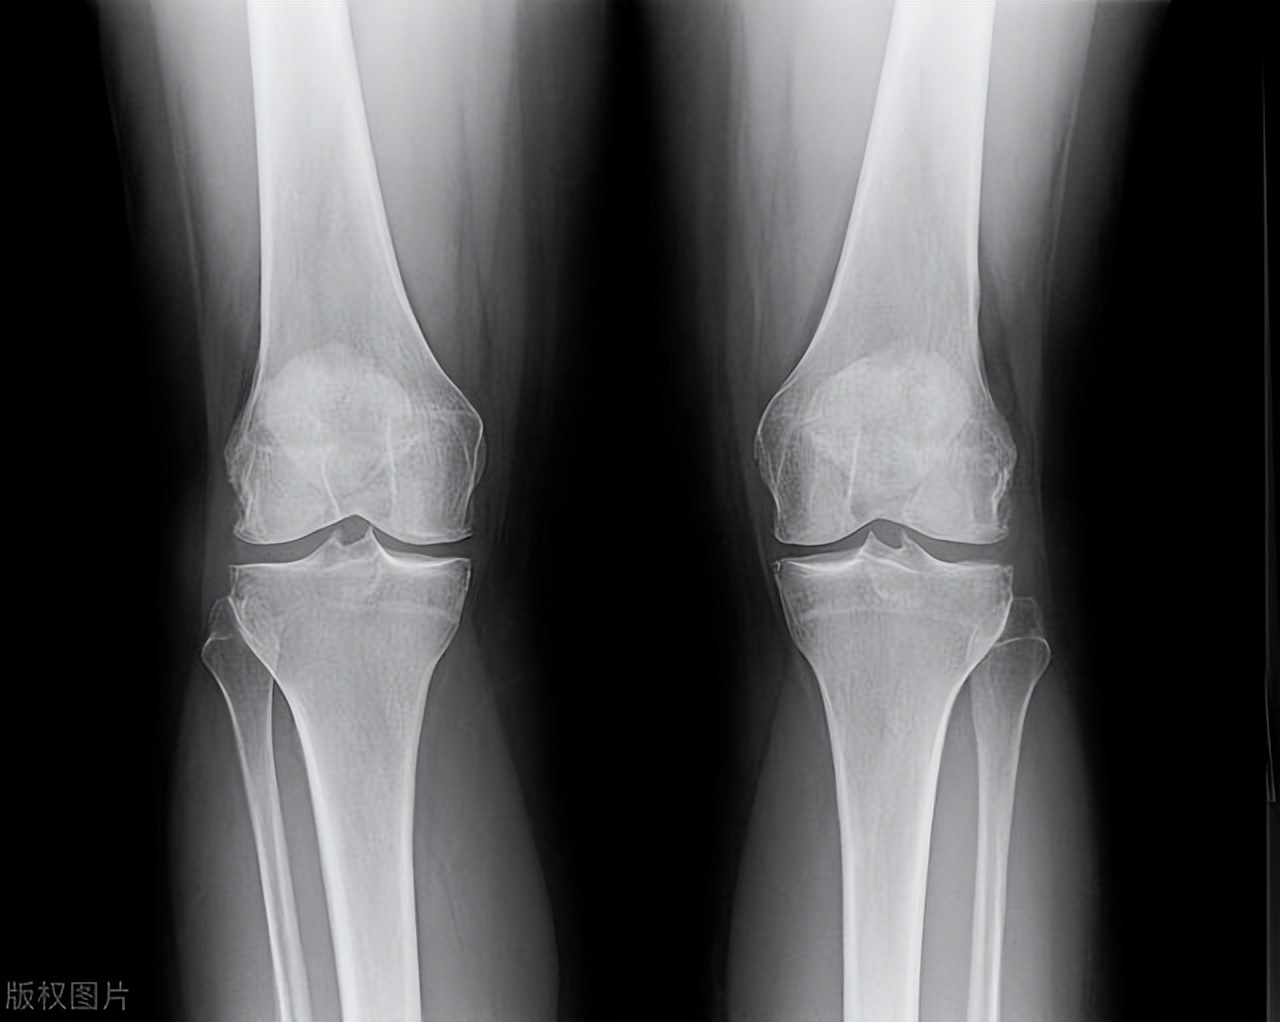

- 膝盖:膝盖是人体最大的关节之一,也是最容易受到压力的关节之一。膝盖骨刺通常发生在膝盖前缘,可能会导致疼痛和不适。

- X射线检查:X射线检查是最常用的检查方法,能够显示骨刺的形状和大小。